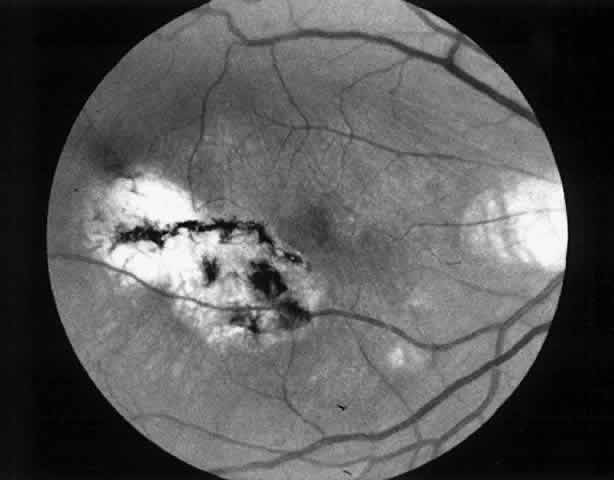

We use positive action horizontal forceps that are angled 130° and have tips 3.2 mm in length.15 The tips are introduced (closed) through the retinotomy, which has usually enlarged slightly during the subretinal manipulation. The objective is to place the opened blades around the stalk or the adhesion, with the membrane in front of the blades. Gentle traction with the blades held closed breaks the connection (Fig. 5). This step is performed slowly and carefully. If traction on the retina is seen, the membrane is released and further separation of the complex from neurosensory retina is accomplished. If excessive tugging and displacement of surrounding RPE is seen, then consideration is given to using the subretinal scissors to cut the stalk rather than breaking it with the forceps. In virtually every case, the membrane (and often the adjacent laser scar) can be removed in one piece. As pathologic examination has confirmed, the abundance of cohesive basement membrane material matrix surrounding occasional capillaries, creates a complex of significant tensile strength.14